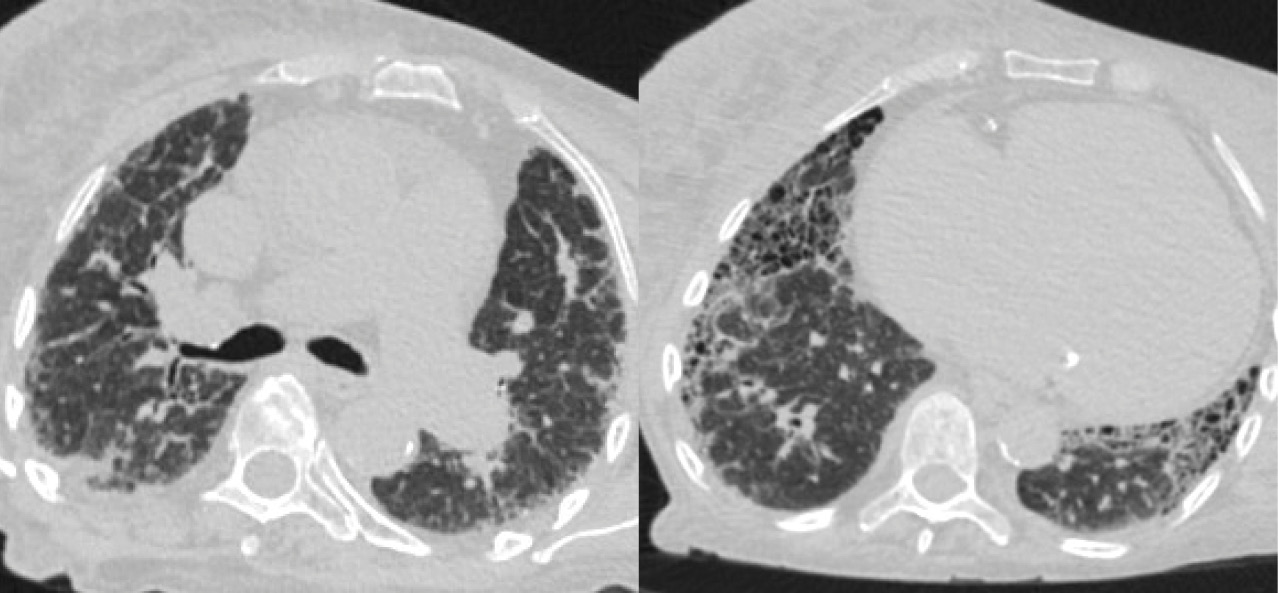

КТ ОГК с контрастированием: КТ-картина интерстициального заболевания легких в стадии формирования «сотового легкого» (рис. 3), малый двусторонний гидроторакс, кардиомегалия. Данных за тромбоэмболию легочной артерии не получено.

Рис. 3. Компьютерная томография органов грудной клетки: аксиальные срезы. Распространенные двусторонние фиброзные изменения на фоне увеличившихся зон «матового стекла», множественные мелкие полостные образования с формированием «сотового легкого», многочисленные бронхоэктазы и бронхиолоэктазы, что соответствует картине возможной обычной интерстициальной пневмонии или фибротическому типу неспецифической интерстициальной пневмонии

На фоне нарастающей полиорганной недостаточности пациентка скончалась. При патоморфологическом исследовании выявлена обычная интерстициальная пневмония с формированием «сотового легкого». Осложнениями стали хроническое легочное сердце, декомпенсация (толщина стенки правого желудочка – 0,8 см, желудочковый индекс – 0,8 (отношение массы правого желудочка к массе левого желудочка в норме 0,4–0,6)), хроническая сердечная недостаточность, двусторонний гидроторакс (по 400 мл в правой и левой плевральных полостях), дистрофия печени, почек, миокарда; признаки портальной гипертензии – спленомегалия (масса 350 г), асцит (1500 мл), гепаторенальный синдром. Данные аутопсии (гистологического исследования) представлены на рис. 4, 5.